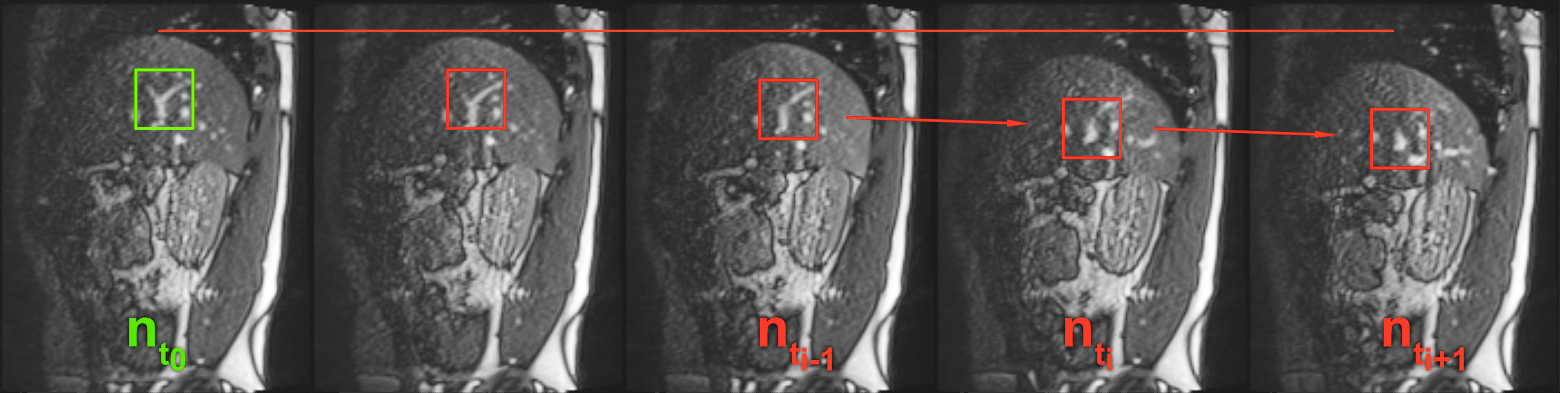

To increase robustness against the out-of-plane motion, we propose to apply template updates within the reference sequence. In Fig 6, one can see how the appearance of a vessel cross-section can change during a breathing cycle. The method starts with the templates that were defined manually on reference frame nt0subscript𝑛subscript𝑡0n_{t_{0}}. Then, for each following navigator frame ntisubscript𝑛subscript𝑡𝑖n_{t_{i}} that was captured at time point tisubscript𝑡𝑖t_{i}, the templates get automatically updated, as follows: The positions of all tracked vessels in ntisubscript𝑛subscript𝑡𝑖n_{t_{i}} are found with subpixel precision using the templates from time point ti1subscript𝑡𝑖1t_{i-1}. Then a new set of templates is cut from ntisubscript𝑛subscript𝑡𝑖n_{t_{i}} based on the position of the matched templates. The template position is updated with floating-point precision. The updates ensure that changes in the appearance of the tracked vessel are represented in the updated templates. The subpixel precision in the updates is needed to avoid drift during the update.

Refer to caption

Fig 6: Out-of-plane motion and template updates. The figure shows a series of navigator slices. The green rectangle denotes a typical ROI that was manually determined as a template. In the red rectangles, one can see how the vessel cross-section changes its appearance during the breathing cycle. For viewing purposes only, the images gradation curve was altered globally to enhance contrast.